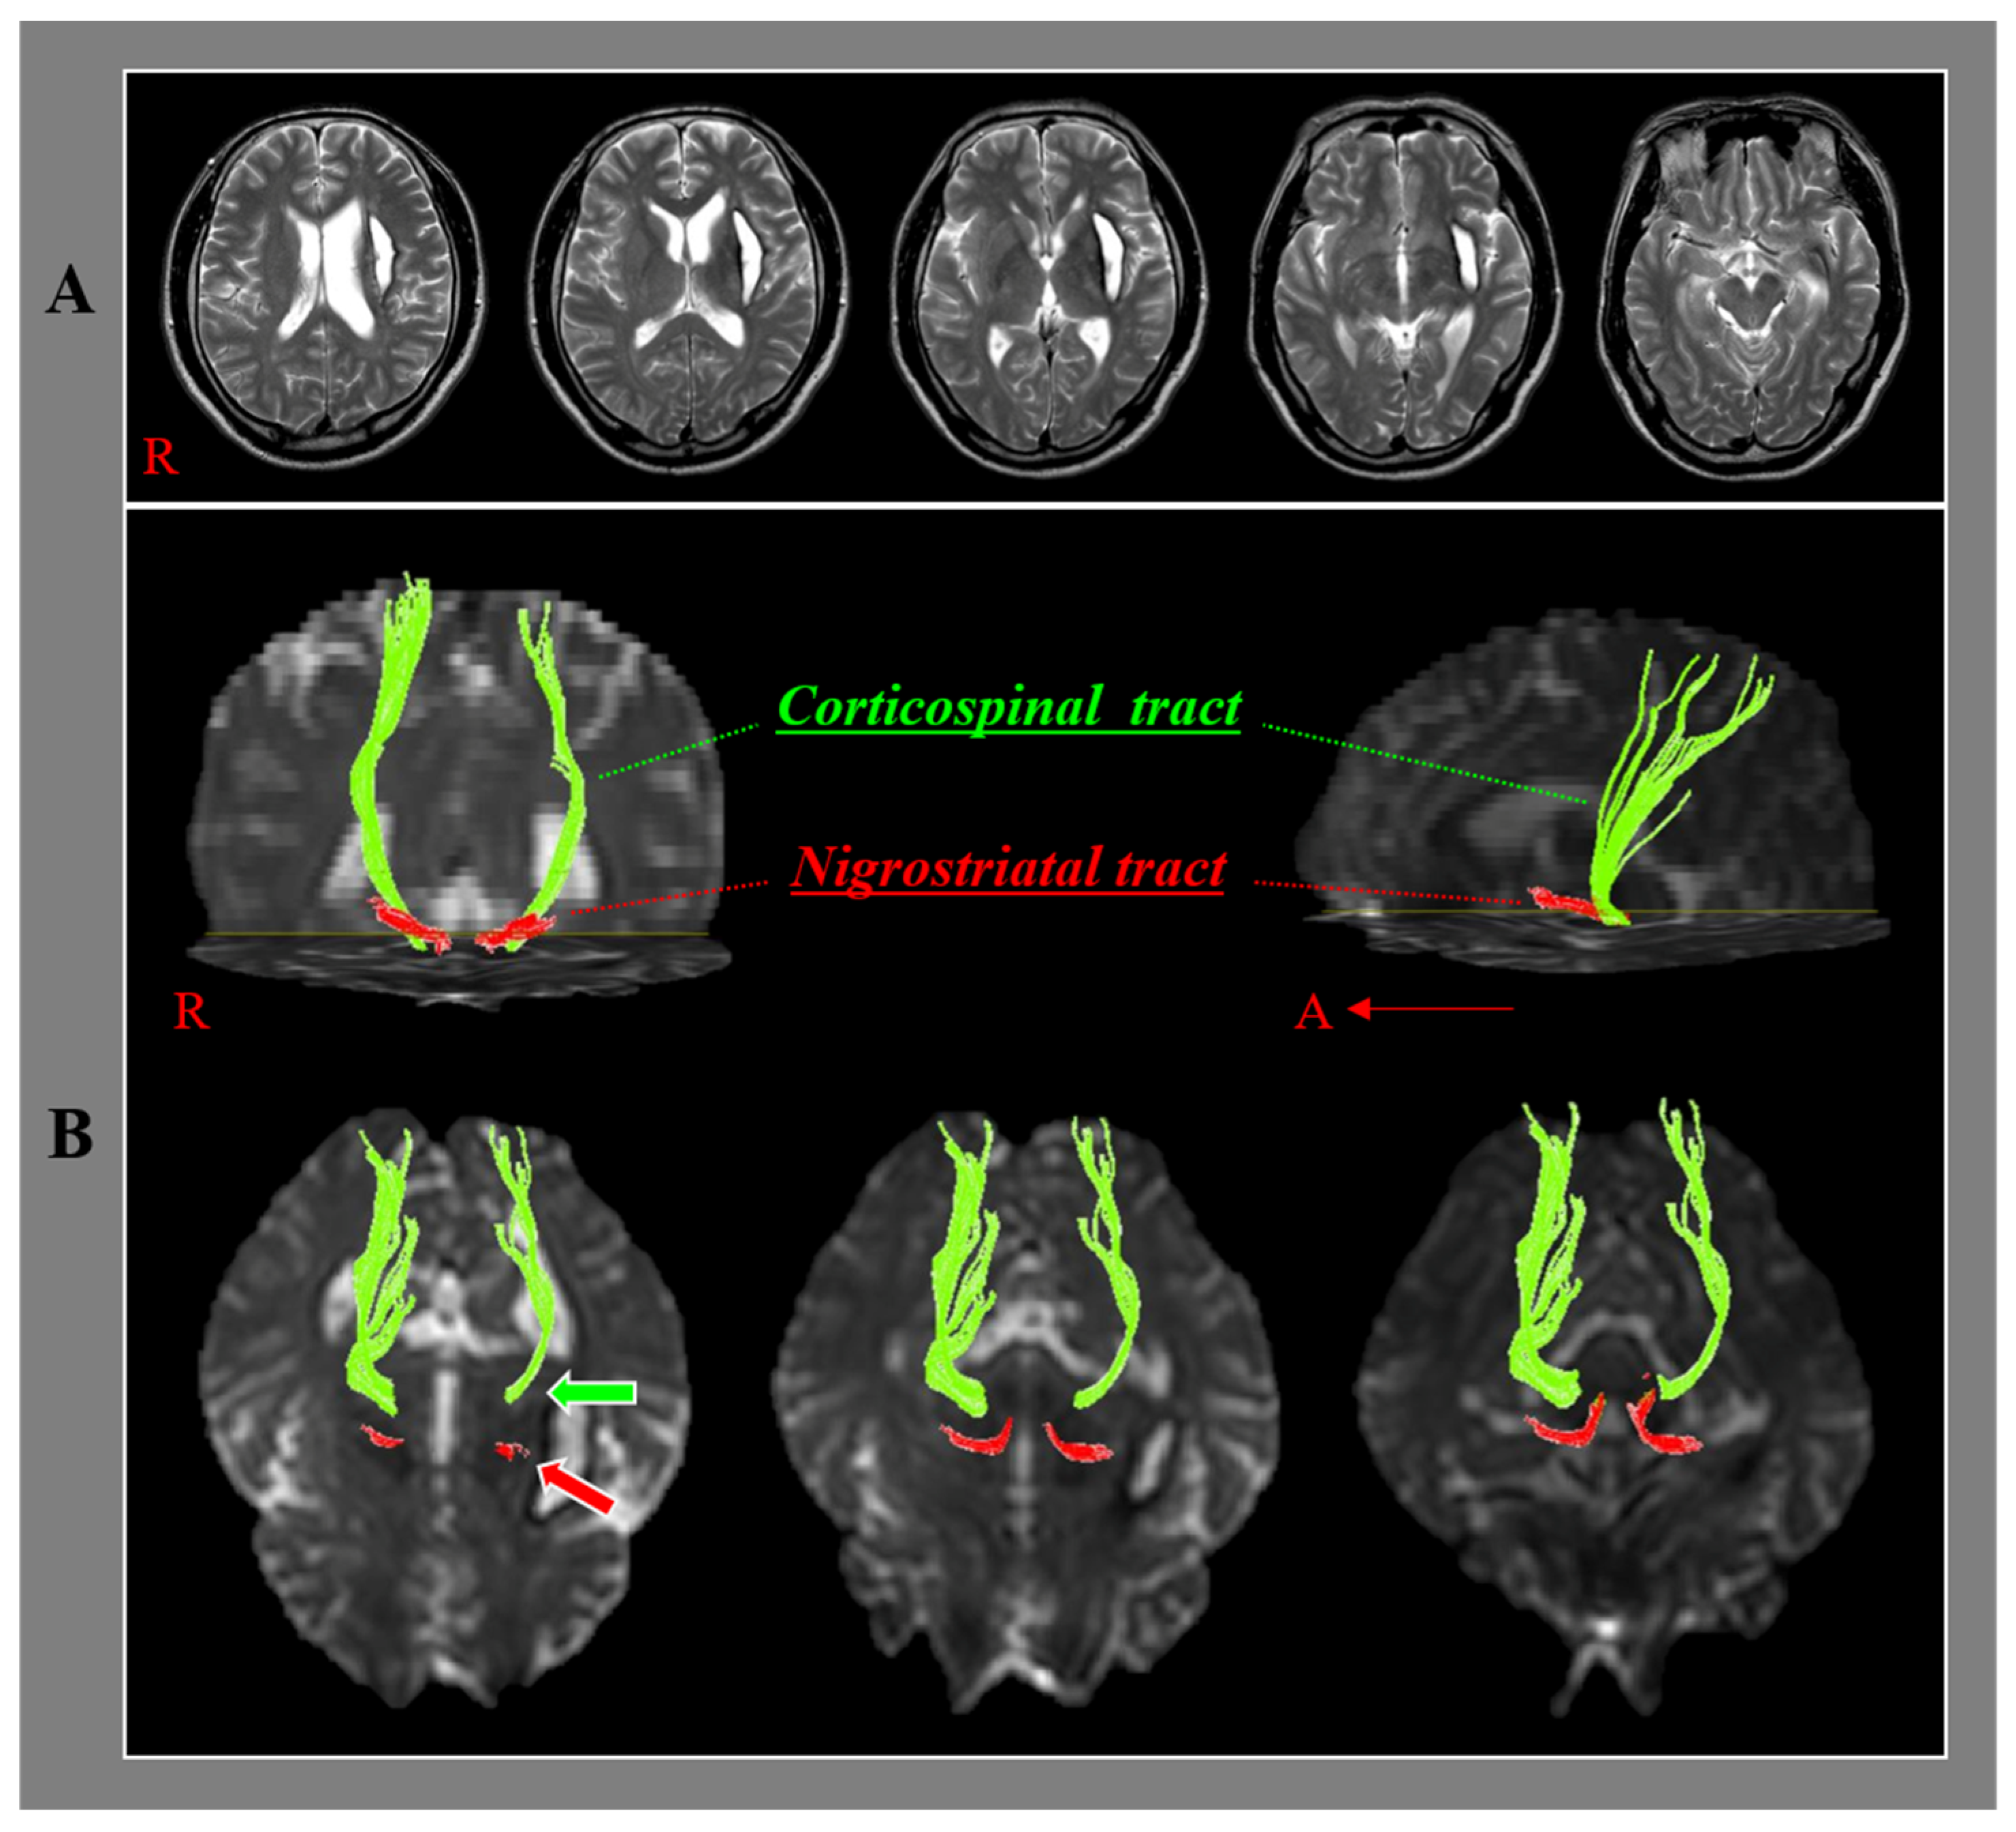

Relationship of the Nigrostriatal Tract with the Motor Function and the Corticospinal Tract in Chronic Hemiparetic Stroke Patients: A Diffusion Tensor Imaging Study